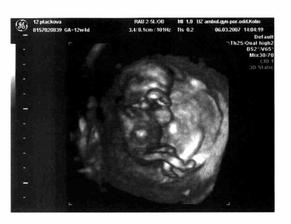

Na naše 4 výročí jsme si dali s manželem ten nejkrásnější dáreček - miminko na svět vykoukne kolem 11.9........... 6.9. se nám narodila princeznička Vaneska v 6:00 s váhou 3,485 kg a 50 cm.